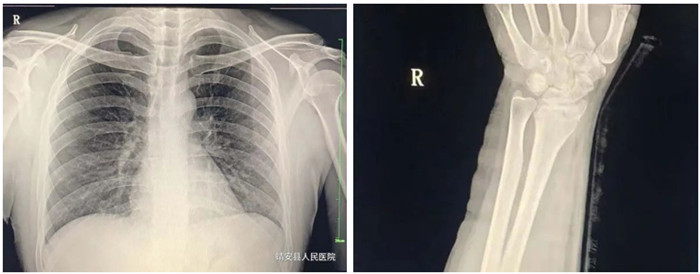

動態DR攝影

動態DR影像

普愛醫療PLX8500D數字化醫用X射線攝影系統(動態DR)具有動態、靜態圖像采集兩種攝影方式。17*17動態大平板,900W高清像素,可以更有效覆蓋檢查范圍、降低檢查所需時間和曝光,從而確保提升影像檢查效率,有效避免廢片、漏診、誤診、二次拍攝、多次重復曝光等不良隱患情況的發生。采用超寬34寸液晶顯示器,解放雙屏雙工作站的束搏,實現采集圖像和回放圖像并列顯示,使臨床圖像效果對比更直觀,操作更方便快捷。